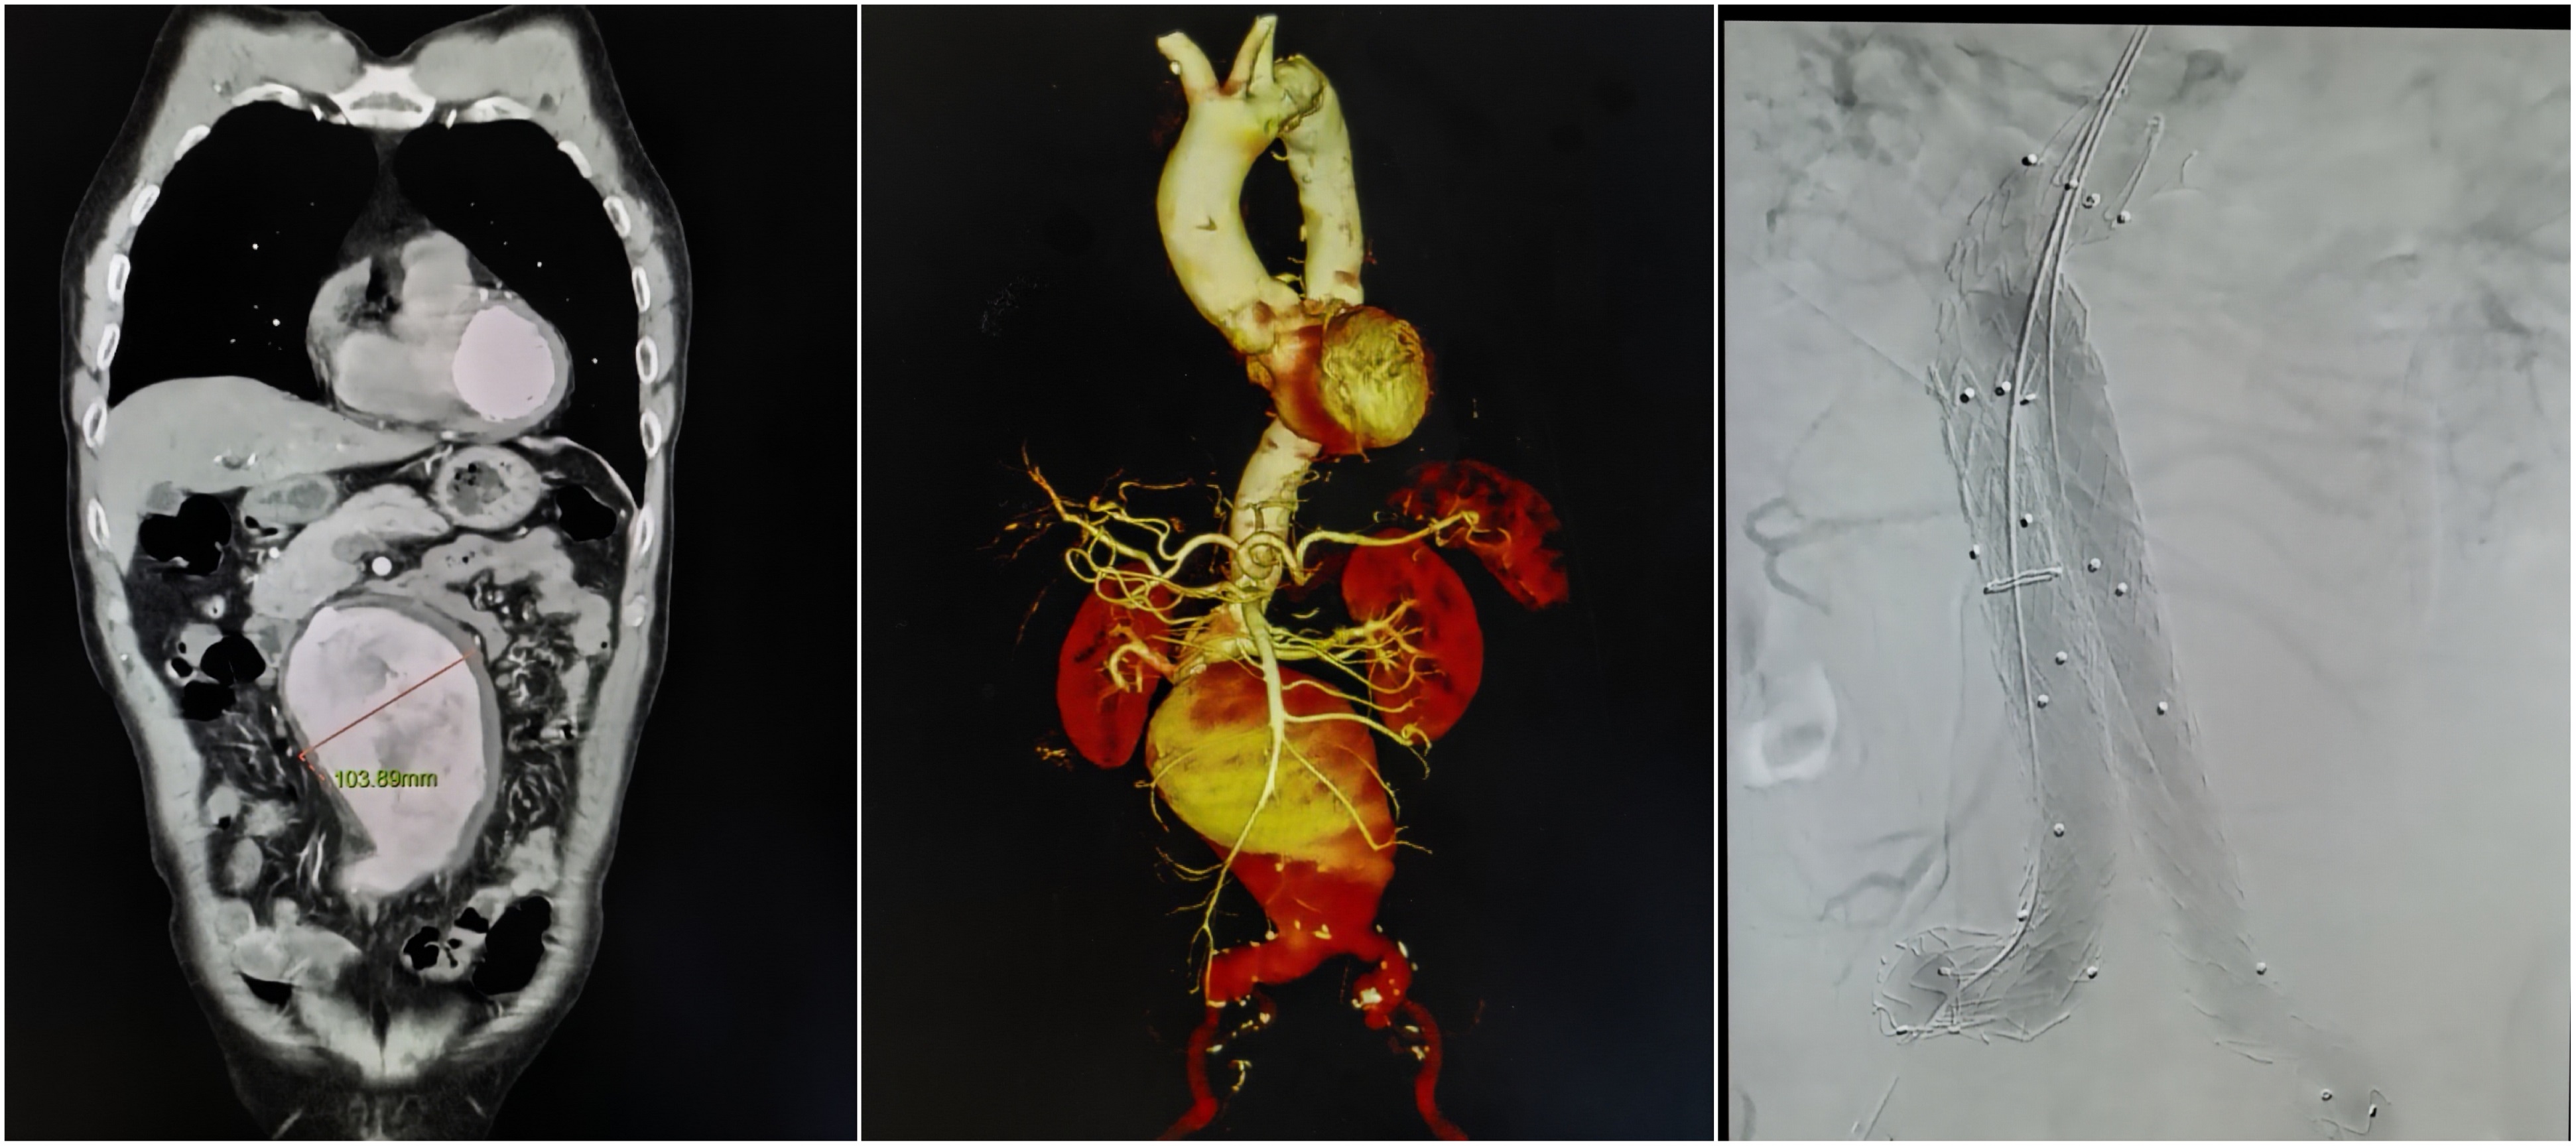

4月23日,中南大学湘雅三医院上演一场惊心动魄的生命急救。血管外科团队高效联动、精准施治,成功为一名患有直径达10厘米的巨大腹主动脉瘤患者完成急诊微创腔内隔绝术,以精湛技术拆除体内“定时炸弹”。

患者因腹胀就诊湘雅三医院,CT意外发现腹主动脉巨大动脉瘤,濒临破裂,病情危急,血管外科总住院薛碧晨第一时间赶赴急诊科接诊,血管外科副主任徐宏博迅速启动危重动脉瘤急救绿色通道,在急诊科、麻醉科、复合手术室大力配合下,争分夺秒完成术前准备。随后,血管外科主任姚凯带领徐宏博、王智超、薛碧晨组成的“拆弹部队”仅用一个多小时,通过三个小于1cm的小切口完成微创介入手术,成功隔绝动脉瘤,复查无任何内漏,手术圆满成功。术后患者生命体征平稳,恢复情况良好,于今日从ICU顺利转回普通病房,恢复下地行走。

手术前后的动脉瘤对比